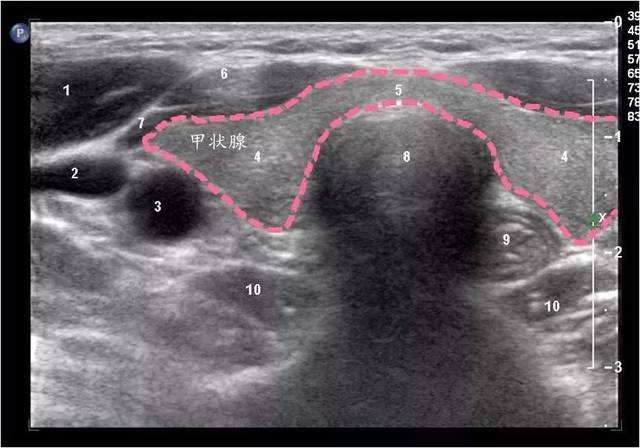

鉴于甲状腺结节通常没有明显的症状,很容易被忽视,所以体检时一定要做颈部触诊。甲状腺结节大多比较隐蔽,多数人是在结节较大时被体检医生触诊“摸出来”的。不过触诊很难明确结节的性质,通常需要甲状腺超来查明结节的具体情况。

通过超声检查可以了解结节的很多细节,如果有下面任何一种情况:

1、微钙化

2、边界不规则

3、纵横比>1

请一定要重视,马上找专科医生就诊

如果是下面的情况:

1、纯囊性

2、海绵状回声

3、边界清晰

4、点状或短棒状血流信号

放松心情,每6-12个月复查超就行。